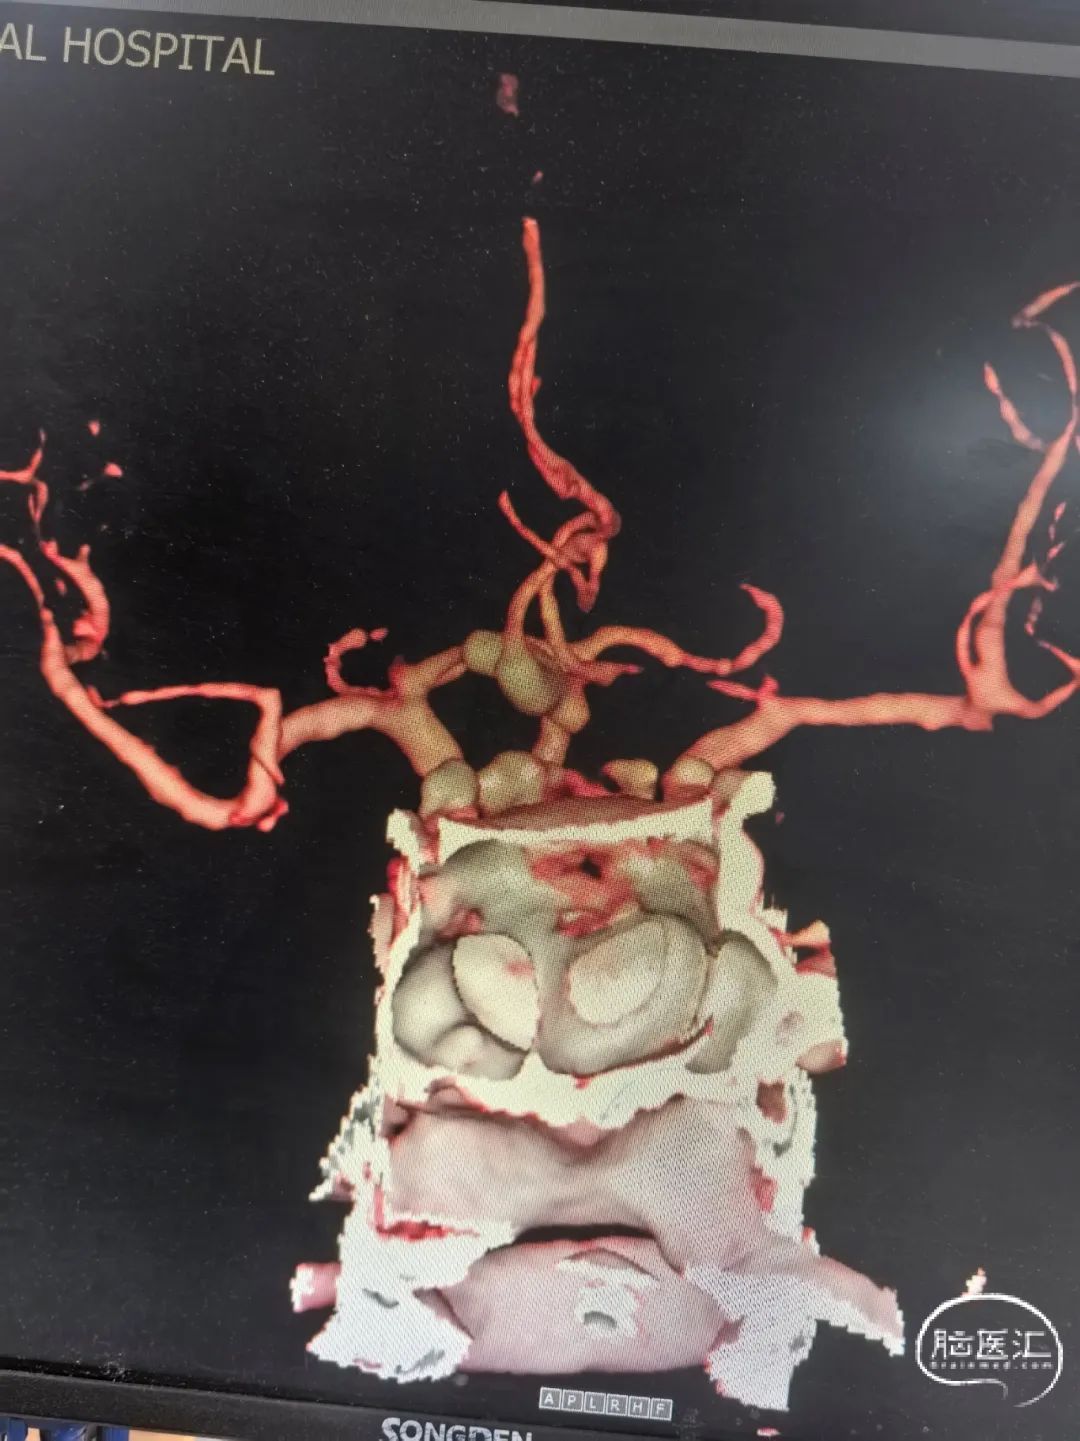

2025-1-19 DSA造影3D重建及方案讨论:

DSA造影3D重建测量

拟行脑动脉瘤密网支架置入术。

2.5mm*15mm Surpass Evolve密网支架,支架锚定区为右侧A2~A1

顺利建立通路,在输送支架到位过程中,XT-27保持稳定。

造影确认远端打开良好,定位后完全释放支架。

支架置入后造影显示,瘤内滞留明显,对侧造影几乎未见瘤内造影剂显影,手术结果满意。

1.该病例通过多方面考虑,选择密网支架植入术手术方案,且锚定区仅为右侧ACA,不影响对侧血流。